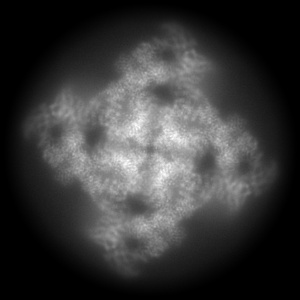

Structure of PKA phosphorylated human RyR2-R420Q in the closed state in the presence of ARM210

Composite map

Single-particle

3.53 Å

Sample: Complex of RyR2-R420Q and Calstabin-2 in the presence of ARM210

Fitted models: 8uxe

Structural basis for ryanodine receptor type 2 leak in heart failure and arrhythmogenic disorders.

Miotto MC , Reiken S, Wronska A , Yuan Q, Dridi H , Liu Y, Weninger G , Tchagou C, Marks AR

(2024) Nat Commun , 15 , 8080 - 8080